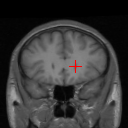

Figure 6: Example comparison among VTN ADDD + inv (c/d), Elastix (e/f), ANTs (g/h) and VoxelMorph-2 (i/j). (a) sections of the fixed image (a CT liver scan); (b) sections of the moving image (another CT liver scan); (c/e/g/i) sections of the warped images and landmark distances; (d/f/h/j) sections of the warped segmentations (white for the fixed and semi-transparent red for the warped) and segmentation IoUs. Crosses indicate the projection of landmarks (L2, L3 and L4 from top to bottom), yellow (lighter) for one in the fixed image, red (darker) for the corresponding one in the moving/warped images. Best viewed in color.

Figure 6 compares different methods listed in Table II, where three landmarks are selected and the sections of the volumes at the height of each landmark in the fixed image are rendered. This means the red crosses (landmarks in the moving and warped images) indicate the projections of the landmarks onto those planes. It should be noted that though the sections of the warped segmentations seem to be less overlapping with those of the fixed one, the Segmentation IoU is computed for the volume and not the sections. It might well be the case that the overlap is not so satisfactory when viewed from those planes yet is better when viewed as a volume. Similarly, overlapping red and yellow crosses do not necessarily imply overlapping fixed and warped landmarks as they might deviate along z𝑧z-axis.